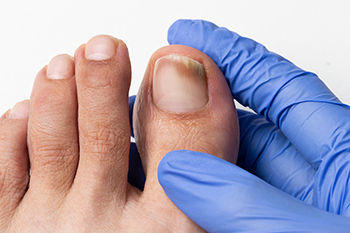

Toenail fungus can cause the toenails to become brittle and yellow. They can gradually harden and become thicker, causing difficulty in having them properly trimmed. This unsightly foot condition is caused by a fungal infection, and is considered to be contagious. This type of fungus lives and thrives in warm and moist environments, consisting of shower room floors, public swimming pools, and similar areas. The fungus can enter the body through tiny cracks in the skin, and it is beneficial to wear appropriate shoes while in these types of areas. A diagnosis is performed by extracting a small sample of the nail. After confirmation is received, treatment can begin. There are various methods that can accomplish this, and it is strongly suggested a podiatrist is contacted as quickly as possible who can prescribe proper medication.

If left untreated, toenail fungus may spread to other toenails, skin, or even fingernails. If you suspect you have toenail fungus it is important to seek treatment right away. For more information about treatment, contact Cary Golub, DPM of New York. Our doctor can provide the care you need to keep you pain-free and on your feet.

Symptoms

- Warped or oddly shaped nails

- Yellowish nails

- Loose/separated nail

- Buildup of bits and pieces of nail fragments under the nail

- Brittle, broken, thickened nail